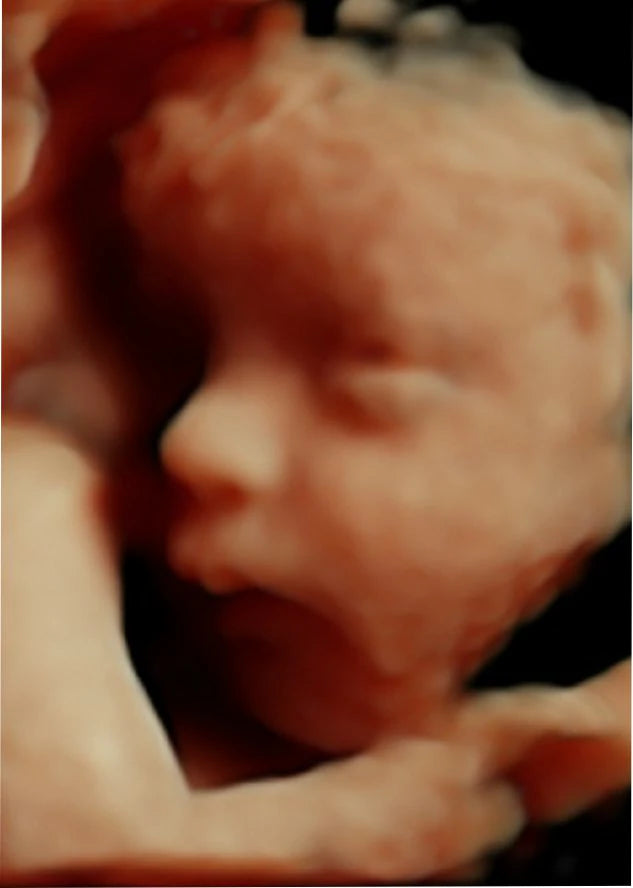

El ultrasonido obstétrico 4D HD es una innovadora técnica de imagenología que utiliza ondas de sonido para generar imágenes tridimensionales en alta definición de su bebé dentro del útero. Esta tecnología avanzada le permite observar los movimientos, gestos y rasgos faciales de su bebé en tiempo real, ofreciendo una experiencia emocionante y conmovedora durante el embarazo.

Imagen: Imagen de un bebé en el útero obtenida a través de un ultrasonido 4D HD.